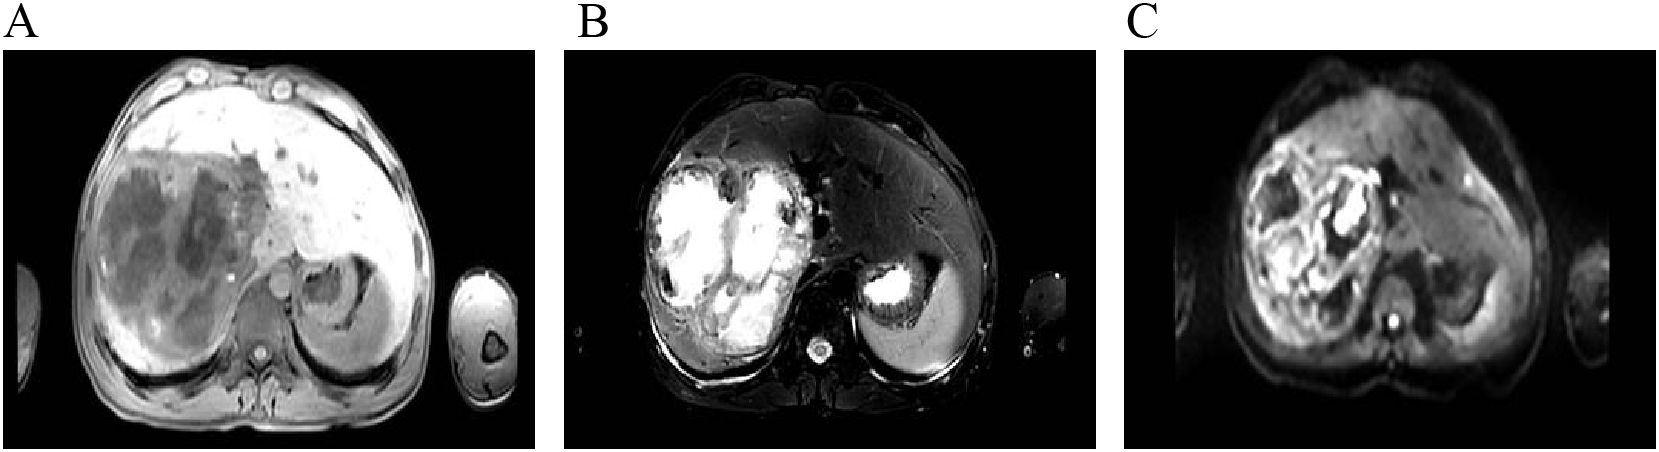

Introduction: Intrahepatic papillary neoplasm of the bile duct (IPNB) with invasive carcinoma is a rare cholangiocarcinoma with most frequent site of origin being intrahepatic bile ducts. Given its rarity and nonspecific clinical presentations, accurate diagnosis plagues clinicians to improve patient outcomes. Case presentation: We present a case of a 31-year-old male who initially exhibited fever. Routine ultrasonography and computed tomography (CT) revealed a large mass in the right liver lobe, suggesting a high likelihood of an infectious lesion. However, multidisciplinary discussion offered a variety of possible scenarios. The patient subsequently underwent an extend right hepatectomy (ERH), and histopathological examination suggested a intrahepatic IPNB with invasive adenocarcinoma. Clinical discussion: The diagnosis and management of IPNB remain challenging, particularly in patients who present with atypical clinical symptoms and lack significant abnormalities in laboratory tests. Early imaging plays a critical role in guiding the diagnostic process. However, a comprehensive diagnostic speculations, clinical expertise, and even invasive detections are essential for establishing a definitive diagnosis and determining the appropriate treatment strategy. Given the potential to invasive carcinoma, early detection and resection are vital to improve prognosis.